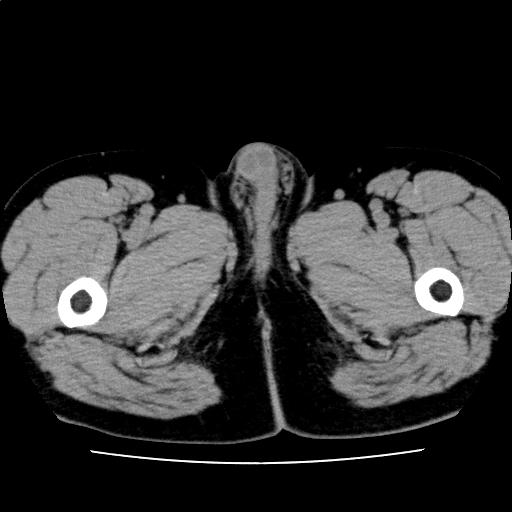

【読影指南】症例画像12

GPT、gGPT高値の精査。飲酒なし。

年齢: 50歳

性別: 男性

検査部位: 腹部

検査種別: CT

CTスライス画像

CTスライス1